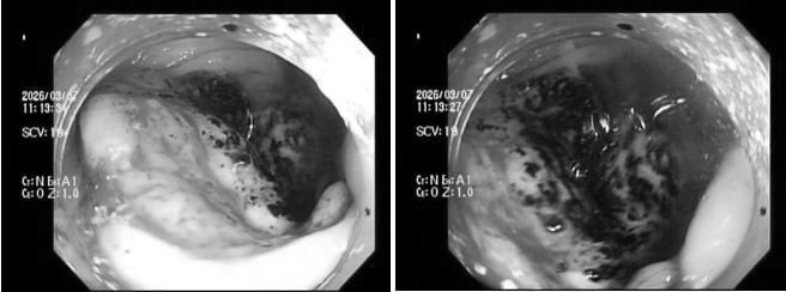

Tuy nhiên, kết quả xét nghiệm máu lại cho thấy tình trạng thiếu máu nghiêm trọng. Bác sĩ chỉ định nội soi đại trực tràng tiếp tục phát hiện một khối u dạng vòng nhẫn đang chảy máu âm ỉ. Kết luận giải phẫu bệnh khiến anh H. bàng hoàng với hai chữ ung thư.

Trường hợp chị P.V.P.U. (34 tuổi) cũng tương tự. Khi thấy vợ xanh xao bất thường, chồng chị đã đưa đi khám. Trước đó, bản thân chị chỉ thỉnh thoảng cảm thấy đau bụng nhẹ thoáng qua rồi hết nên nghĩ là rối loạn tiêu hóa thông thường, do stress. Tuy nhiên, kết quả thăm khám ban đầu lại cho thấy chị bị thiếu máu nặng. Ngay sau đó, bác sĩ chỉ định nội soi đại tràng và phát hiện một khối u lớn, bề mặt loét, rất dễ chảy máu. Kết quả mô bệnh học khiến cả hai vợ chồng sững sờ: Ung thư đại trực tràng.

| Hình ảnh nội soi ung thư. Ảnh: BSCC. |